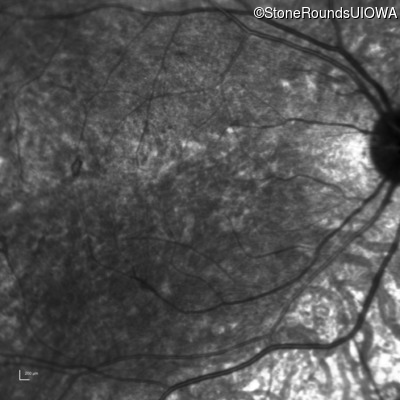

Age at visit: 8 years

OD OS

This 8 year old girl had normal vision until age 6 when she failed a school vision screening. That year, she was able to play softball well, but this year she often loses sight of the ball and is often hit by it.